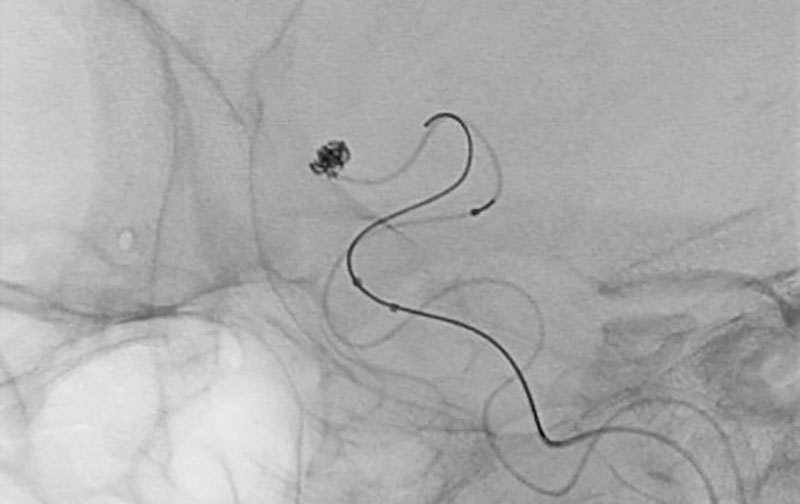

No.1628 手術前

No.1628 手術中

No.1628 手術後